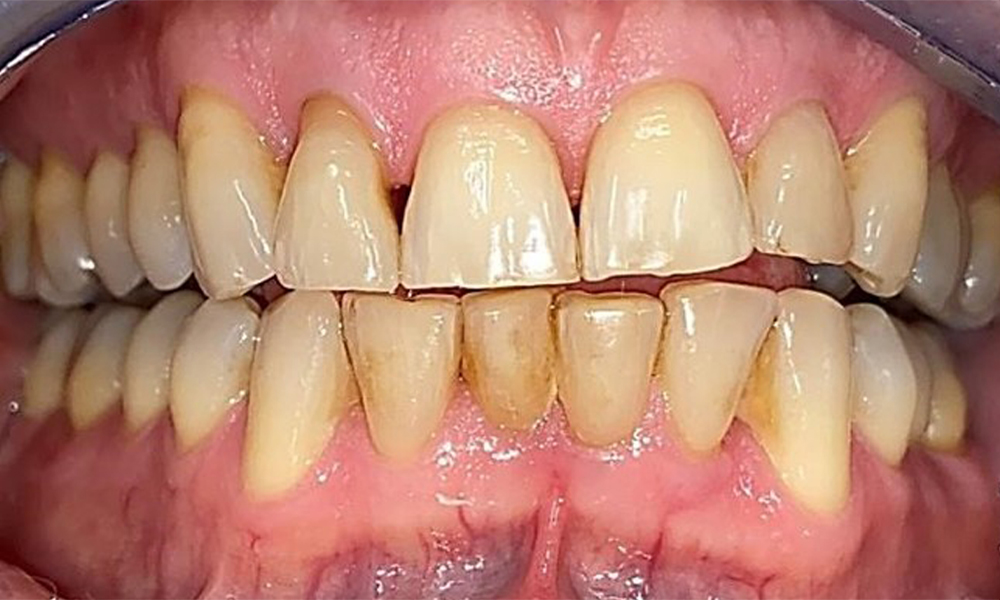

The patient has a full dentition with 28 teeth, which includes amalgam and composite fillings in the molar and premolar regions. There is a visible clinical marginal gap present on tooth 14. Tooth 27 has an adequate gold inlay. There are also generalized attritions and abrasions. (Fig. 2, Fig. 3, Fig. 4, Fig. 5, Fig. 6)

The patient has stage II, grade B periodontitis (5). At 1 to 3 mm, the clinical probing depths were within the physiological range. Localized probing depths of 5 mm were observed on the mesiopalatal aspects on both 17 and 27. There are generalized recessions of 1–3 mm with partial loss of the interdental papillae (Fig. 2, Fig. 3, Fig. 4)